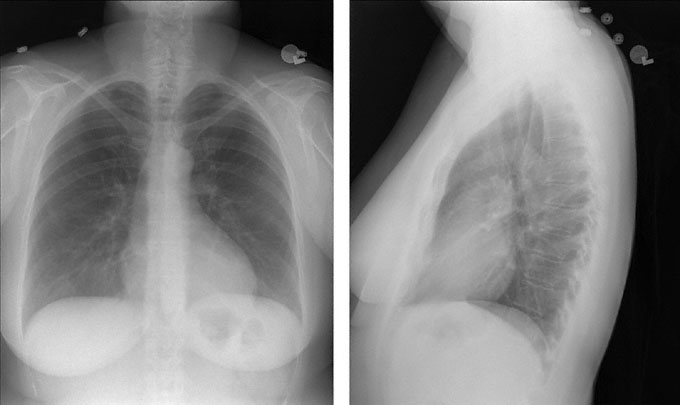

A 27-year-old woman with a 9-year history of systemic lupus erythematosus comes to the emergency department because of sharp, left-sided chest pain and mild shortness of breath that began yesterday. The patient also reports mild pain in her left calf for the past 2 days. She reports no recent trauma and has not had cough, fever, or chills. Medical history is otherwise unremarkable and she takes no medications. Vital signs are temperature 37.1°C (98.8°F), pulse 108/min, respirations 20/min, and blood pressure 126/72 mm Hg. Pulse oximetry on room air shows an oxygen saturation of 95%. Auscultation of the chest discloses no abnormalities. There is mild tenderness to palpation over the left calf, which is 2 cm larger in circumference than the right calf. The remainder of the physical examination discloses no abnormalities. Chest x-rays are shown. Which of the following is the most appropriate next step in diagnosis?